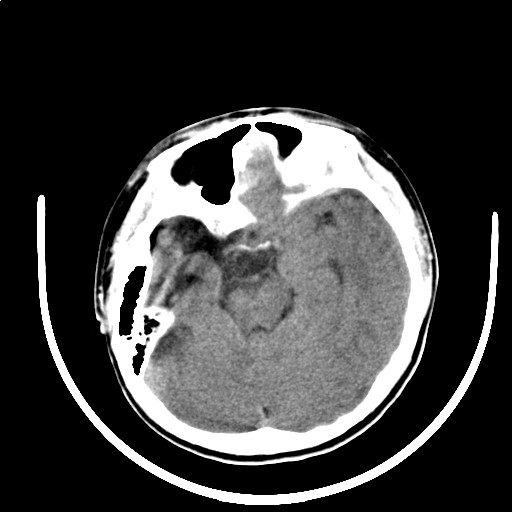

标题: PED3416:F,12Y,智力下降,学习成绩差,8个月时发过高烧。

右侧大脑发育不良伴动静脉畸形。

右侧半球萎缩,软化,多量脑回样钙化,考虑颅面血管瘤病,建议dsa检查

右侧半球萎缩,软化,多量脑回样钙化,同侧颅盖板障增宽,考虑颅面血管瘤病,建议dsa检查与化脓性脑膜炎后遗改变鉴别。